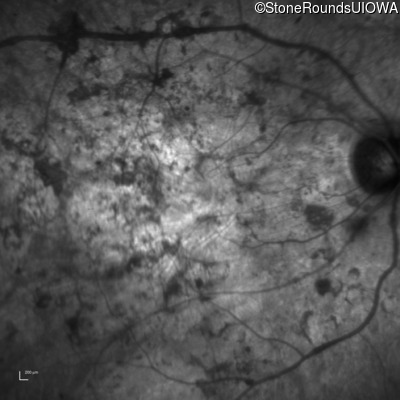

Optical Coherence Tomography - Left - Hand Motion

Exemplar / OCT Stack